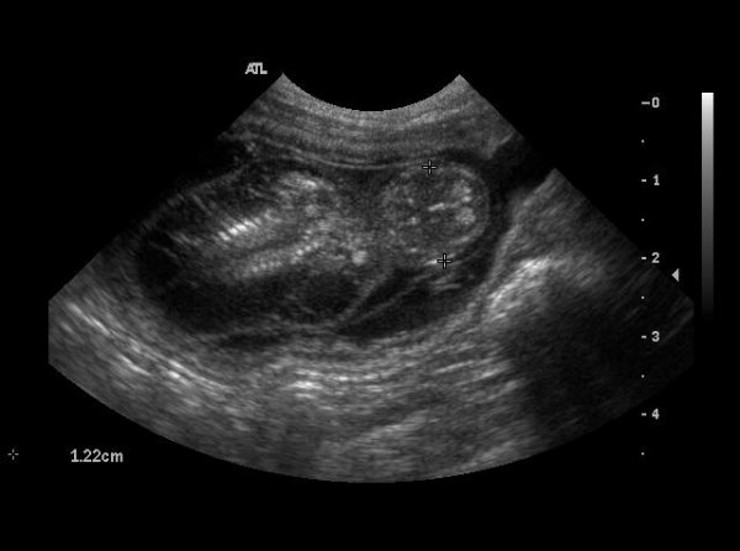

Ultrasound - pregnancy diagnosis